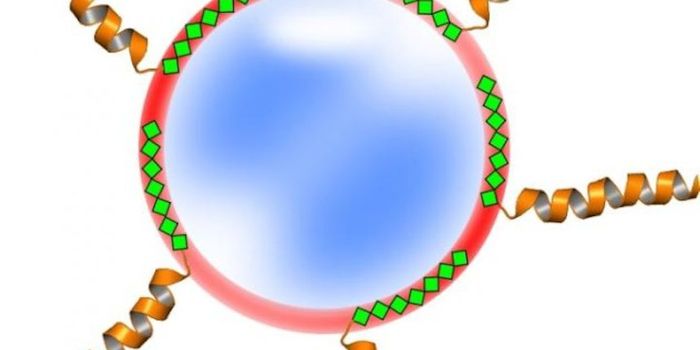

APR 20, 2015Cell & Molecular BiologyFastening protein-based medical treatments to nanoparticles isn't easy.

With arduous chemistry, scientists ca ... -